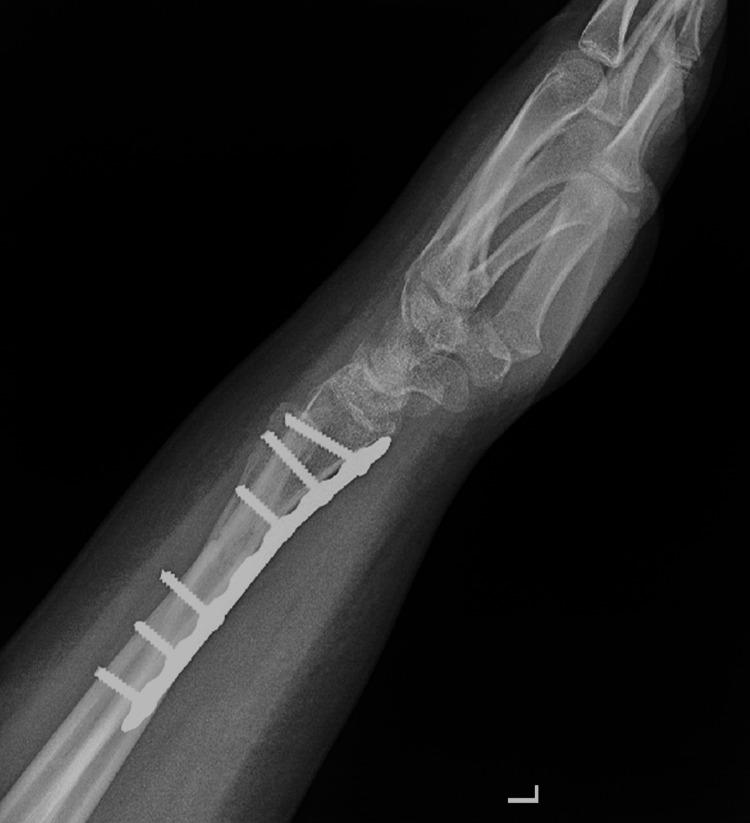

Fractures of the forearm are common among children and adolescents. Radial shaft fracture with dislocation of the distal radioulnar joint (DRUJ), called Galeazzi fracture, is unusual in pediatrics. The Galeazzi-equivalent fracture is a variant of the classic Galeazzi fracture that occurs in children and adolescents. It is a radius fracture associated with a distal ulnar displaced physeal injury without dislocation of the DRUJ. Our patient was a male, aged 15 years, who visited our emergency department after falling off a scooter onto his left hand. Left wrist X-rays showed a displaced Galeazzi-equivalent fracture. After a trial of close reduction, an X-ray showed a displaced and unstable fracture pattern. The patient was subsequently hospitalized for surgical intervention. Open reduction and internal fixation (ORIF) with a plate and screw were used for the radius fracture. The ulna fracture was irreducible; therefore, ORIF with two crossed smooth Kirschner wires (K-wires) was performed. Complete bone union was achieved, and he had a normal range of motion six months postoperatively. The patient is now able to perform daily and sports activities. At two-year follow-up, complications such as DRUJ instability or joint deformity did not occur. In conclusion, open reduction is desired for patients with malalignment or older patients who have a lower potential for sufficient bone remodeling. Regular serial follow-up sessions are required to assess growth arrest and the occurrence of other complications.

前臂骨折在儿童和青少年中很常见。桡骨干骨折合并下尺桡关节(DRUJ)脱位,即盖氏骨折,在儿科中并不常见。类盖氏骨折是经典盖氏骨折的一种变体,发生于儿童和青少年。它是一种桡骨骨折,伴有尺骨远端骨骺移位损伤,而DRUJ无脱位。我们的患者是一名15岁男性,骑滑板车时左手着地后前来我院急诊科就诊。左手腕X线片显示为移位的类盖氏骨折。试行闭合复位后,X线片显示骨折移位且不稳定。患者随后住院接受手术治疗。桡骨骨折采用钢板螺钉切开复位内固定(ORIF)。尺骨骨折无法复位;因此,采用两根交叉光滑克氏针(K针)进行ORIF。术后6个月实现了完全骨愈合,患者活动范围正常。患者现在能够进行日常和体育活动。在两年的随访中,未出现DRUJ不稳定或关节畸形等并发症。总之,对于骨折对位不良的患者或骨重塑潜力较低的年长患者,需要进行切开复位。需要定期进行系列随访,以评估生长停滞和其他并发症的发生情况。